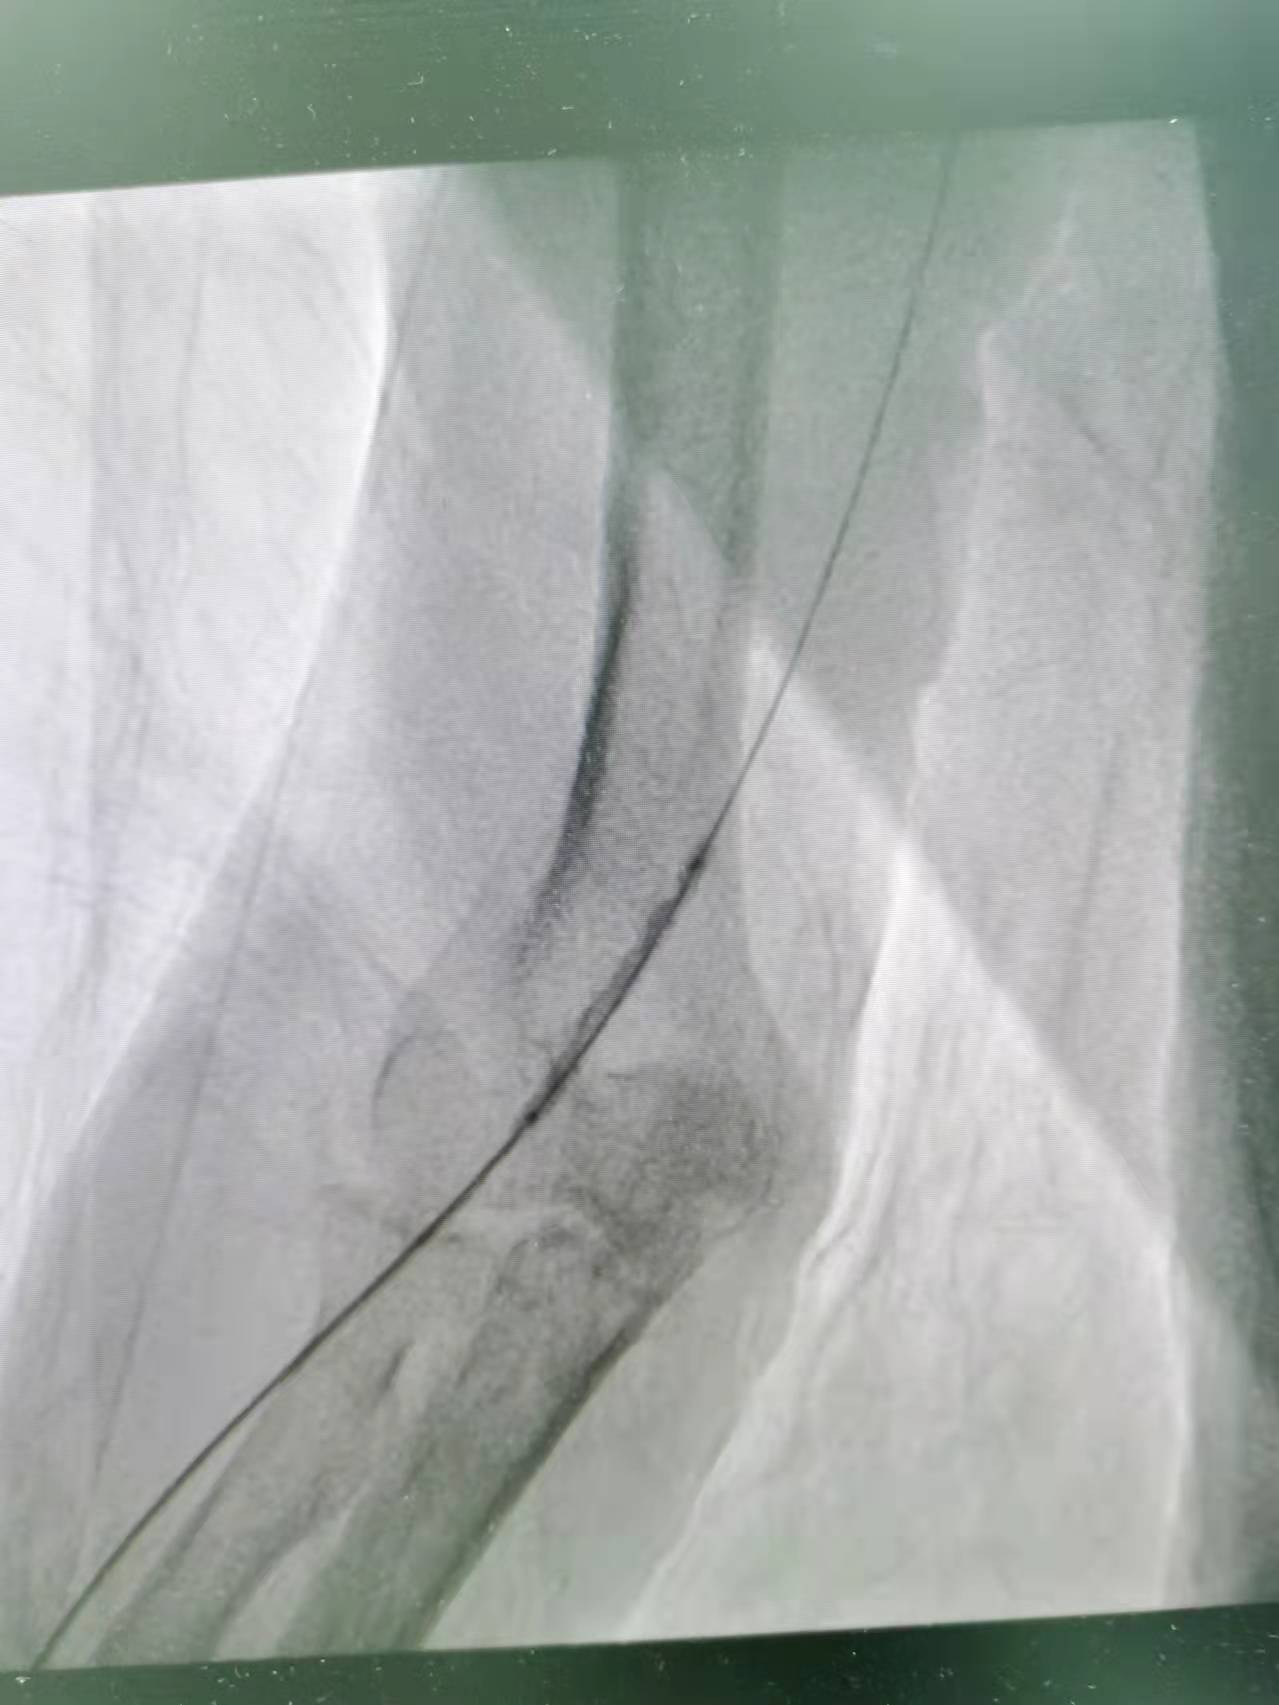

术中,李友河主任及肾内科团队予以在手术部位常规消毒、铺巾、局麻后选择远端桡动脉为穿刺入口,在彩色B超指引下穿刺成功后,按导入血管鞘,血管鞘导入泥鳅导丝,在彩色B超和x线曝光下导丝过内瘘口至头静脉直至贵要静脉近心端再 至上腔静脉,但未入右心房,于以肝素2000U血管注入,影显示内瘘口近心端3cm处头静脉段 重度狭窄, 长约1.2cm;手术过程顺利,术后宗叔血液透析流量良好,可达250ml/min,顺利完成血液透析。目前宗叔已康复出院且内瘘功能良好。

近心端狭窄扩张

近内瘘口狭窄扩张